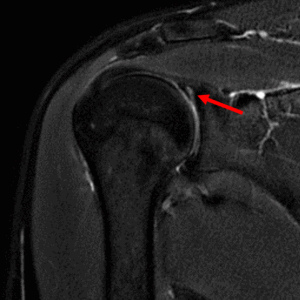

- MRI検査:肩関節唇損傷の状態を確認。他の疾患との鑑別が必要な場合に実施

赤矢印:上方関節唇損傷